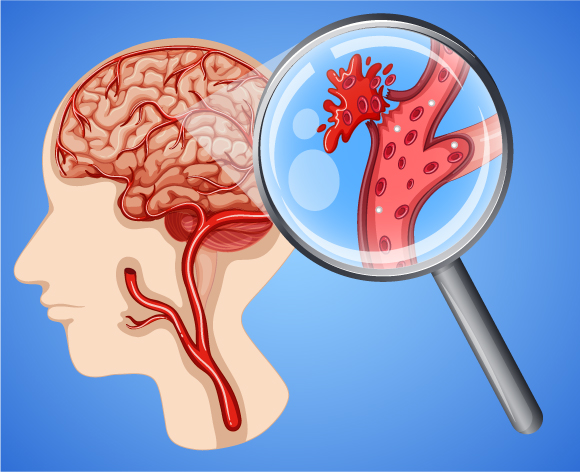

يُصاب عشرة بالمئة من مرضى السّكتات القلبية باِلسّكتة النّزفيّة. يتدفّق الكثير من الدّم، عند انفجار أحد الأوعية الدّمويّة الدّماغيّة، إلى النّسيج الدّماغيّ. تُعطّل هذه الحالة، هي الأخرى، تزويد الدّم بشكل سليم إلى جزء من خلايا الدّماغ، فتموت.

تحدث السّكتة الدّماغيّة النّزفيّة في عشرة بالمئة من الحالات | الرّسم التخطيطيّ: GraphicsRF.com, Shutterstock